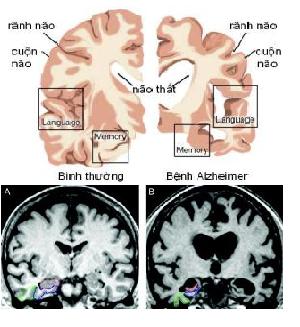

Alzheimer’s disease:

Alzheimer’s disease is the most common form of dementia, accounting for around two-thirds of cases. It causes a gradual decline in cognitive abilities, often beginning with memory loss.

Alzheimer’s disease is characterised by two abnormalities in the brain – amyloid plaques and neurofibrillary tangles. The plaques are abnormal clumps of a protein called beta amyloid. The tangles are bundles of twisted filaments made up of a protein called tau. Plaques and tangles stop communication between nerve cells and cause them to die.